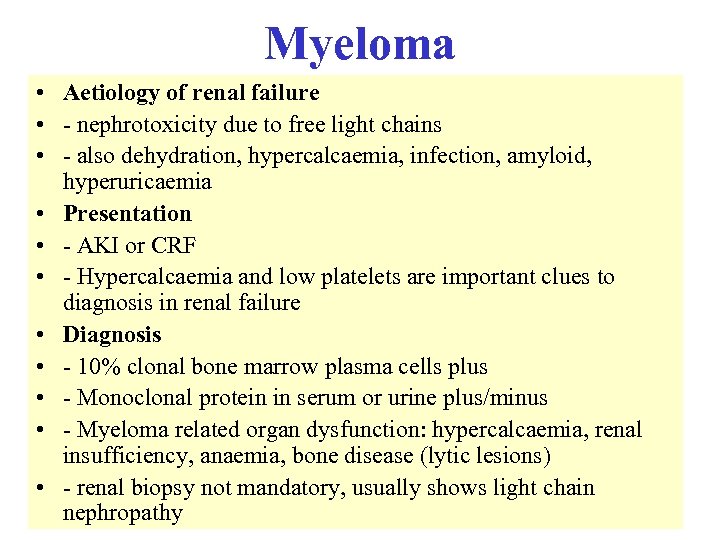

Myeloma • Aetiology of renal failure • - nephrotoxicity due to free light chains • - also dehydration, hypercalcaemia, infection, amyloid, hyperuricaemia • Presentation • - AKI or CRF • - Hypercalcaemia and low platelets are important clues to diagnosis in renal failure • Diagnosis • - 10% clonal bone marrow plasma cells plus • - Monoclonal protein in serum or urine plus/minus • - Myeloma related organ dysfunction: hypercalcaemia, renal insufficiency, anaemia, bone disease (lytic lesions) • - renal biopsy not mandatory, usually shows light chain nephropathy

Myeloma • Aetiology of renal failure • - nephrotoxicity due to free light chains • - also dehydration, hypercalcaemia, infection, amyloid, hyperuricaemia • Presentation • - AKI or CRF • - Hypercalcaemia and low platelets are important clues to diagnosis in renal failure • Diagnosis • - 10% clonal bone marrow plasma cells plus • - Monoclonal protein in serum or urine plus/minus • - Myeloma related organ dysfunction: hypercalcaemia, renal insufficiency, anaemia, bone disease (lytic lesions) • - renal biopsy not mandatory, usually shows light chain nephropathy